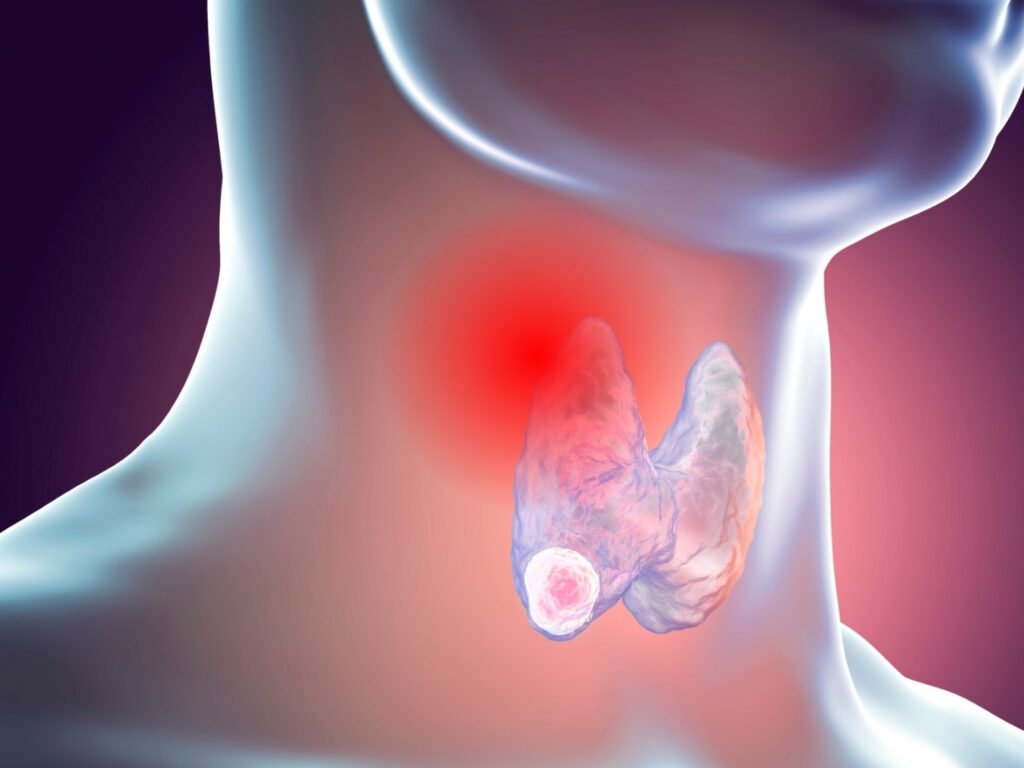

Cirugía de tiroides en 2025: tecnologías que están cambiando la seguridad y precisión del tratamiento

Thyroid